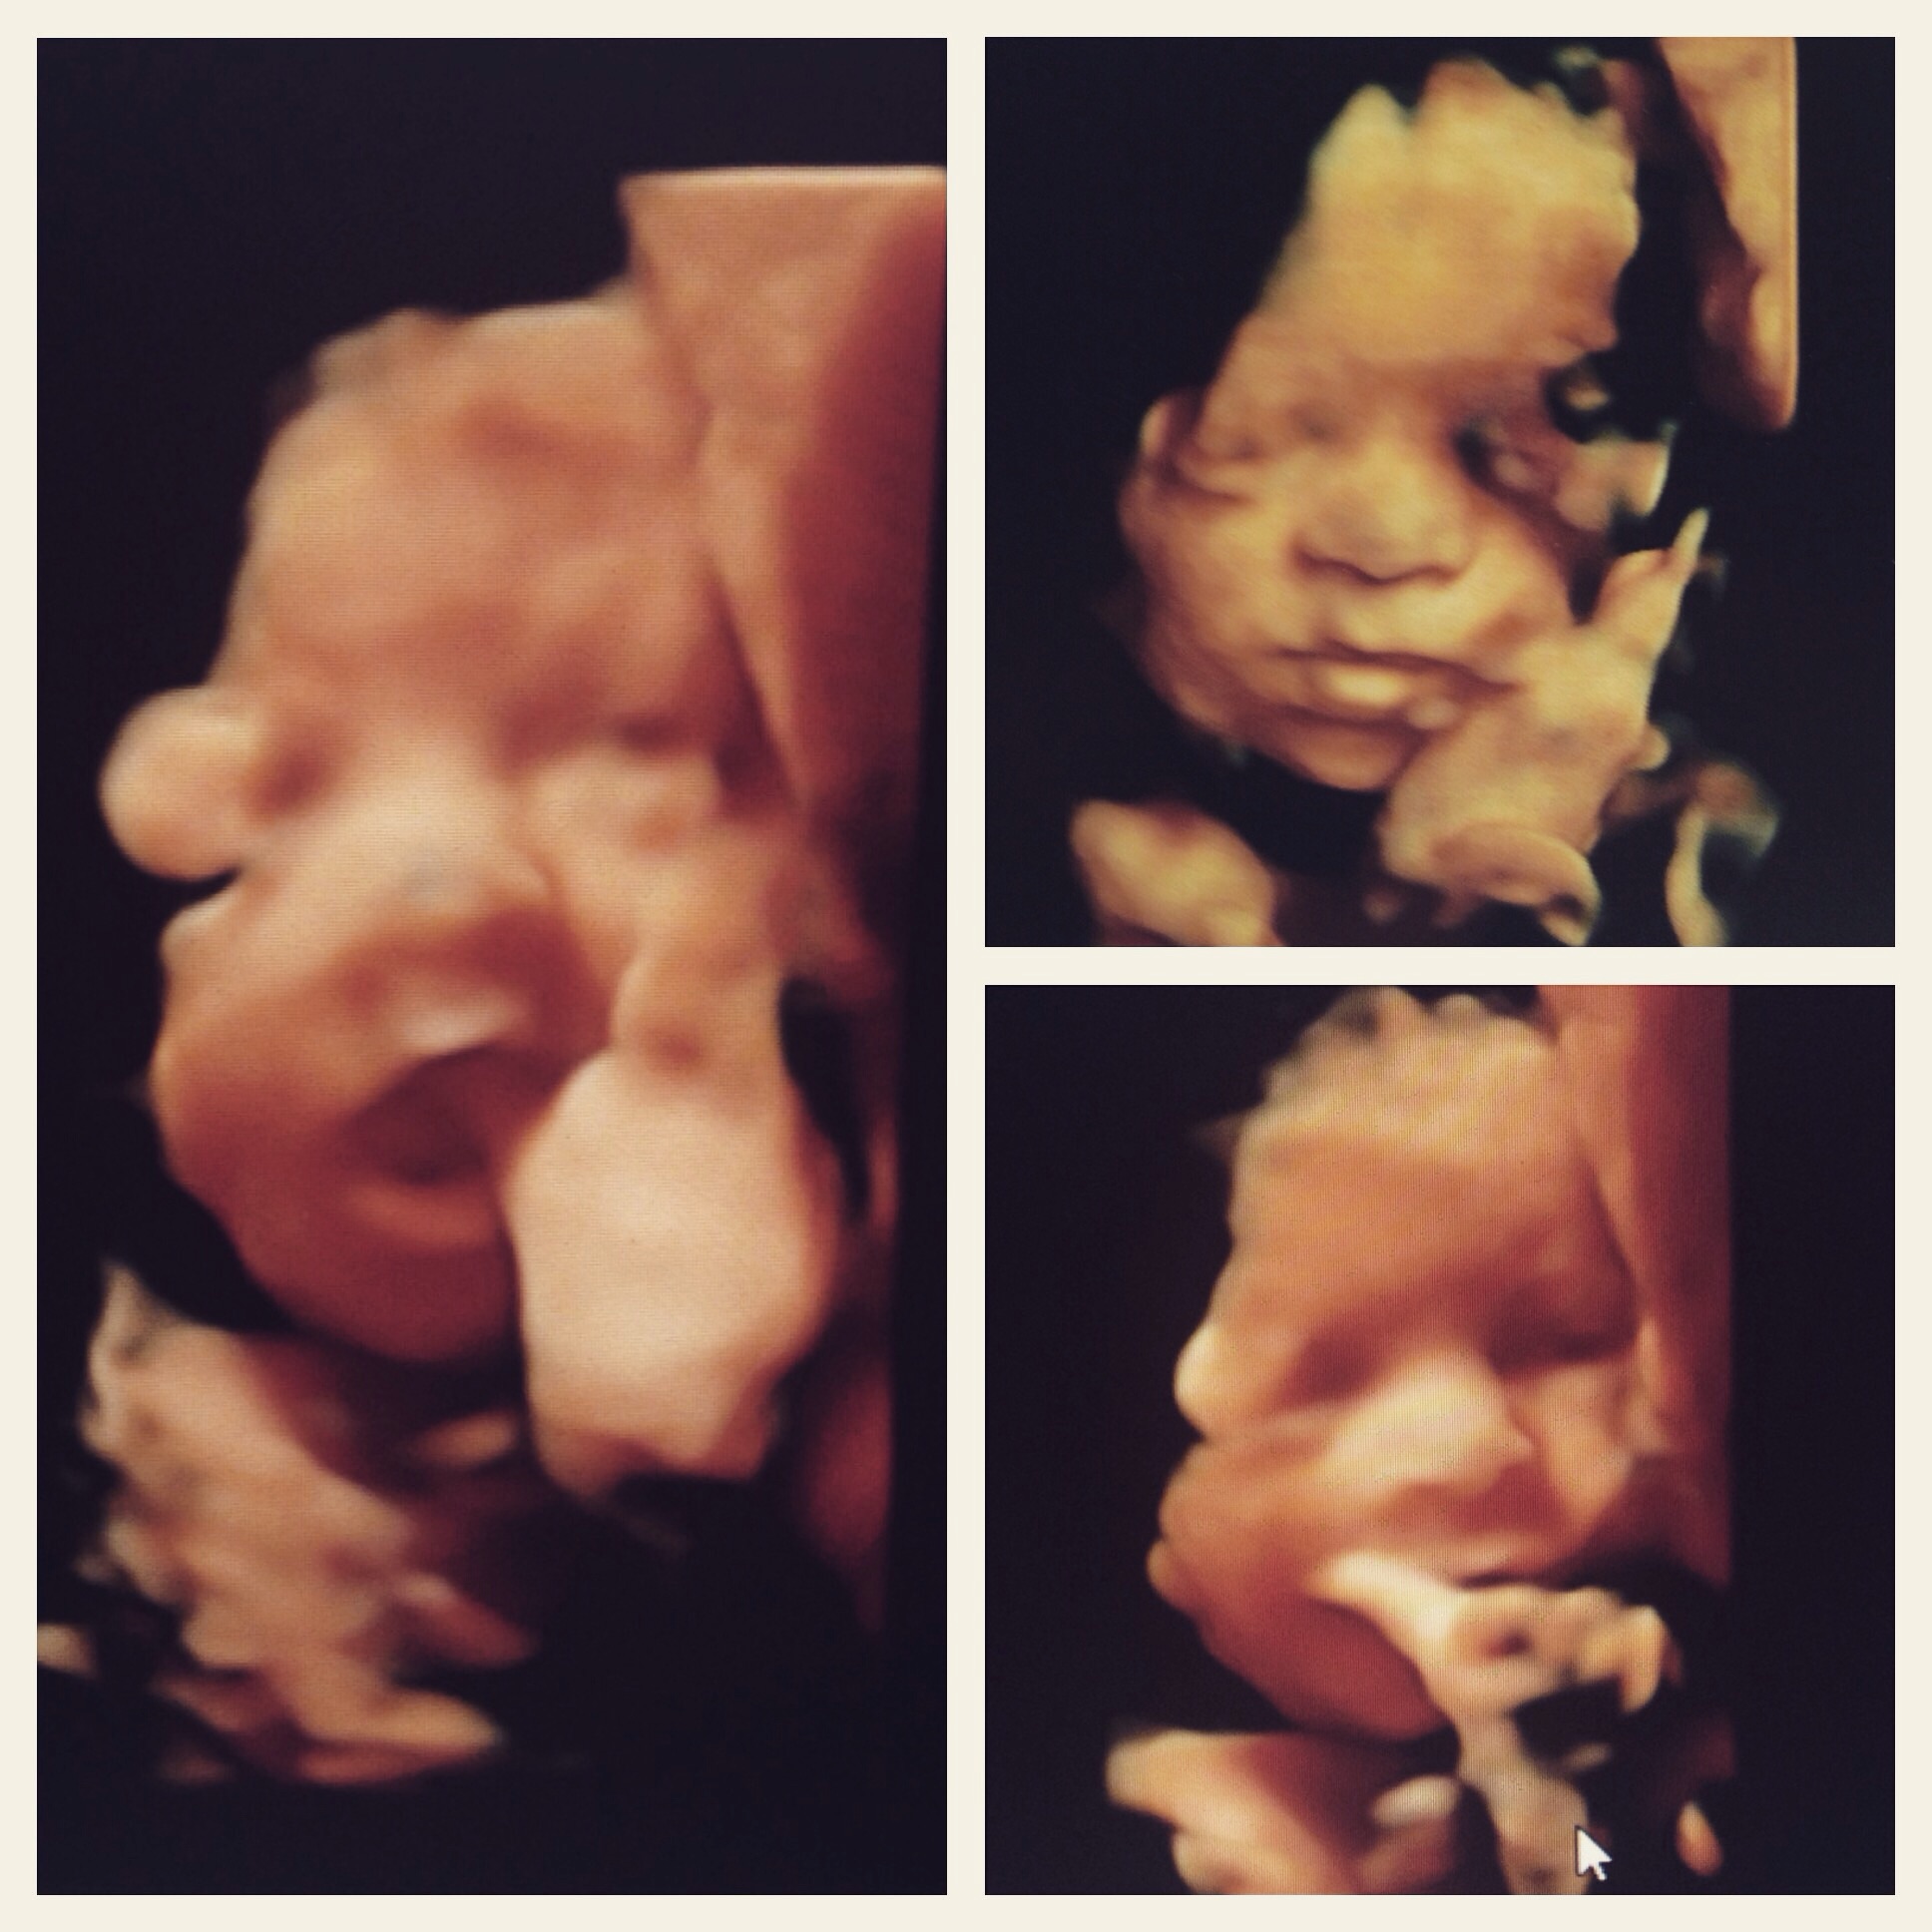

We just had a 3d scan this past Friday at 30 weeks! It was by the far one of the coolest parts of this pregnancy!  We did it for no real reason aside from being first time parents who are crawling out of their skin to meet their little guy. We have a stubborn little boy who likes to keep his hands and feet in front of his face.. managed to still get a few good pictures of him though! If you have the time and the resources, I'd definitely do it.

Matthew Jacob at 30 weeks